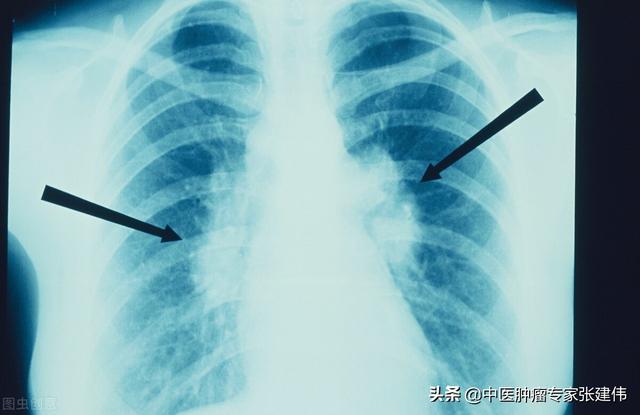

Il existe des nodules pulmonaires multiples et solitaires, et les nodules pulmonaires multiples sont souvent observés à la suite d'une tuberculose ou d'une pneumoconiose, qui sont toutes plus faciles à diagnostiquer avec une anamnèse typique ou une anamnèse du lobe gauche. Les nodules dont nous parlons généralement sont des nodules pulmonaires isolés.

Les examens médicaux étant de plus en plus fréquents, les nodules pulmonaires sont de plus en plus souvent détectés. Les nodules pulmonaires sont un terme d'imagerie, et la définition d'imagerie d'un nodule pulmonaire est une petite lésion bien définie qui est complètement entourée par le parenchyme pulmonaire (Diamètre ≤30mm). La morphologie des nodules est classée comme solide ou sub-solide ; les nodules sub-solides sont eux-mêmes classés en nodules de verre dépoli et en nodules partiellement solides. Les lésions de plus de 30 mm de diamètre sont des masses plutôt que des nodules et ont une probabilité plus élevée d'être malignes.

La définition actuellement acceptée d'un nodule pulmonaire est une ombre pulmonaire focale, arrondie, hyperdense, solide ou subsolide, d'un diamètre ≤3 cm. Ces dernières années, avec l'augmentation de la population examinée par tomodensitométrie à faible dose, la proportion de nodules pulmonaires multiples détectés en plus des nodules pulmonaires isolés a considérablement augmenté. Les nodules pulmonaires multiples se présentent souvent sous la forme d'un nodule pulmonaire unique accompagné d'un ou plusieurs petits nodules. Les nodules pulmonaires multiples sont définis comme 2 lésions ou plus. Les patients présentant des nodules pulmonaires multiples peuvent avoir plusieurs sources de cancer du poumon précoce ou de lésions précancéreuses confirmées chirurgicalement et nécessitant une attention clinique particulière.